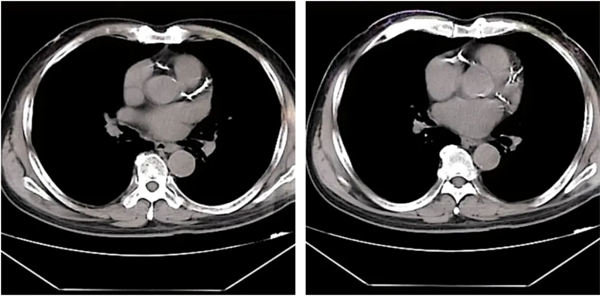

73歲的孟老先生,近期總感覺胸悶氣短,這癥狀斷斷續續三年了,近一周來癥狀加重,就診于我院心血管內二科,患者既往有“持續性心房顫動、高血壓”病史。入院后完善胸部CT提示:冠脈走形區鈣化明顯。

鄭廣生與患者及家屬充分溝通病情后建議行冠脈造影檢查,考慮患者冠脈鈣化嚴重,普通介入治療存在難度,術中需采用旋磨治療充分預處理病變后,再行球囊擴張及支架植入治療。